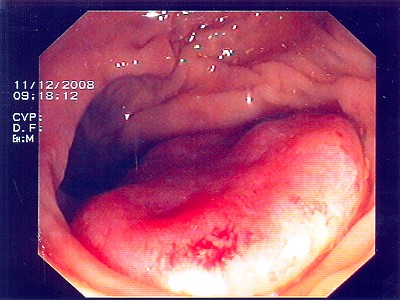

Abb. 1: Bösartiger Tumor des Übergangs von Mast- zu Dickdarm. Hier hilft ausschließlich eine Teilentfernung des Mast- und Dickdarmes. Abb. 1: Bösartiger Tumor des Übergangs von Mast- zu Dickdarm. Hier hilft ausschließlich eine Teilentfernung des Mast- und Dickdarmes.